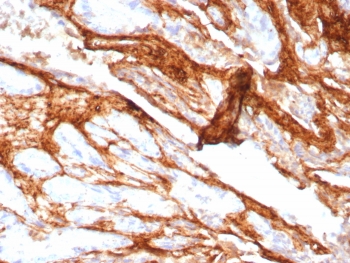

Decorin Antibody Rabbit Monoclonal Prostate IHC. Immunohistochemistry of Decorin antibody in human prostate carcinoma tissue. Formalin-fixed, paraffin-embedded human prostate carcinoma was stained using rabbit monoclonal Decorin antibody (clone DCN/8760R). Heat induced epitope retrieval was performed by boiling tissue sections in 10mM Tris with 1mM EDTA, pH 9, for 20 min followed by cooling prior to staining. HRP-DAB brown chromogenic signal highlights extracellular stromal connective tissue and desmoplastic matrix surrounding malignant glands, consistent with Decorin localization within collagen-rich tumor stroma.